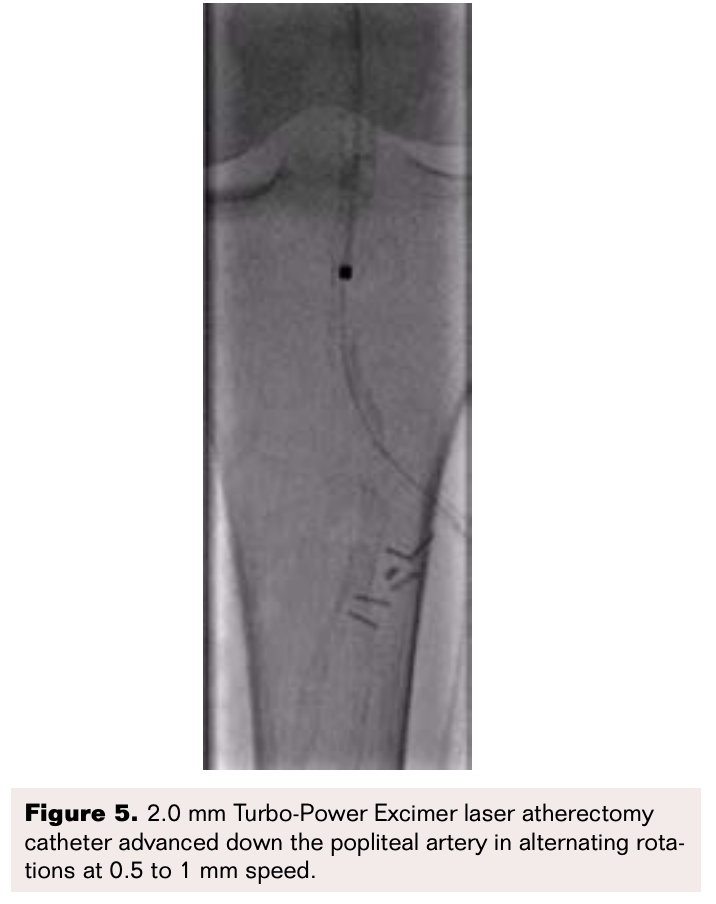

Femoropopliteal lesion modification and plaque debulking was performed using a 2.0 mm Turbo-Power excimer laser atherectomy (ELA) catheter (Philips). Four passes with slow advancements through the lesions at 0.5 to 1 mm/sec, were performed with alternating rotations of the catheter at maximal energy settings (fluence of 60 mJ/mm2 and frequency of 80 Hz) (Figure 5).

ELA devices indicated for peripheral vascular disease interventions include Turbo-Elite and Turbo-Power (Philips) as well as Auryon (AngioDynamics, Inc). Turbo-Power catheter, which exists in 2.0 and 2.3 mm iterations, utilizes a rotating function and has an eccentric wire lumen, with densely packed fiberoptic fibers. The eccentric rotation, which is remotely controlled, allows for directing as well as spinning of the laser catheter as it advances forward. This helps negate dead space to provide more effective ablation, and provide orthogonal displacement of friction for better tracking, especially in calcified vessels. The advancement speed of the laser catheter should ideally be 0.5 to 1 mm per second to ensure the vapor bubble remains in front of the laser catheter, thereby providing optimal ablation. Furthermore, to mitigate potential risk for tissue injury, it is important to apply saline flush infusion during atherectomy to provide optimal lasing environment and prevent contrast and blood from increasing heat absorption, and a to apply a brief 5-10 second pause after every 20 seconds of treatment.